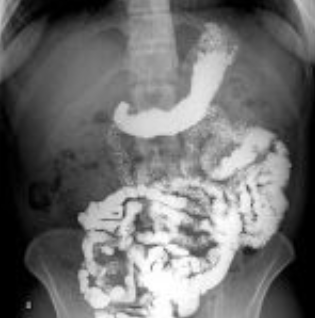

Figura 3: Série com AP, oblíquas e perfil. Fonte: Radiopaedia

Série radiográfica:

- 0 min: Abdome simples (pré-contraste)

- 30, 60, 90, 120 min: Radiografias AP (bipedestia ou decúbito)

- Íleo terminal: Incidências oblíquas e perfil

- Confirmação: Imagem com preenchimento do ceco